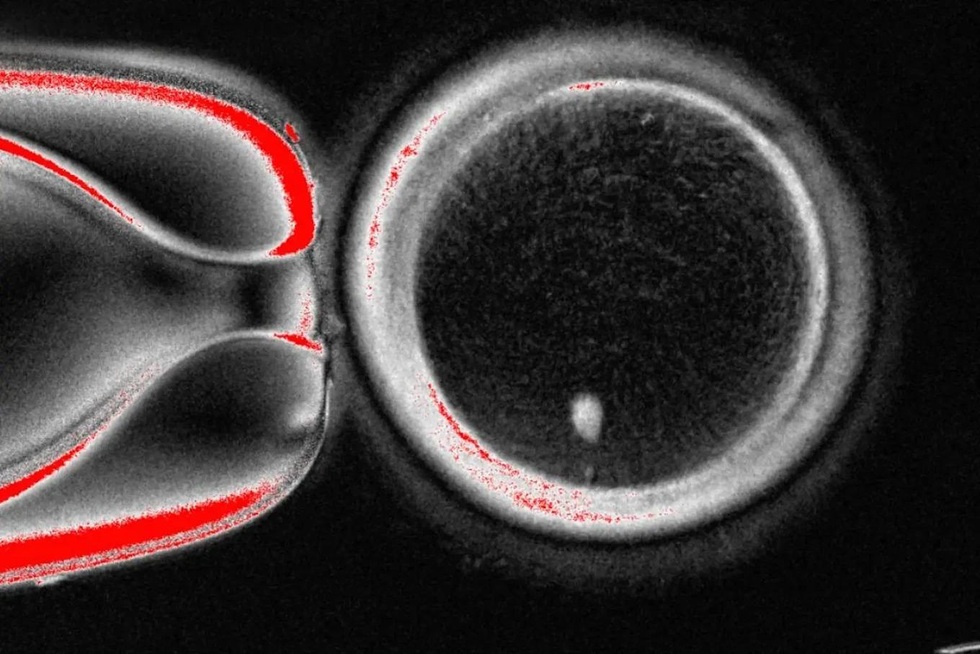

Kết quả là họ thu được một noãn bào (tế bào trứng) mang bộ gen của người hiến tế bào da, đánh dấu lần đầu tiên trứng người được “nuôi tạo” theo phương pháp này.

Hình ảnh do Phòng thí nghiệm Mitalipov, Trường Đại học Khoa học và Sức khỏe Oregon, Mỹ, cung cấp, cho thấy hình ảnh dưới kính hiển vi của một quả trứng người có chứa nhân lấy từ tế bào da (ảnh: AP).